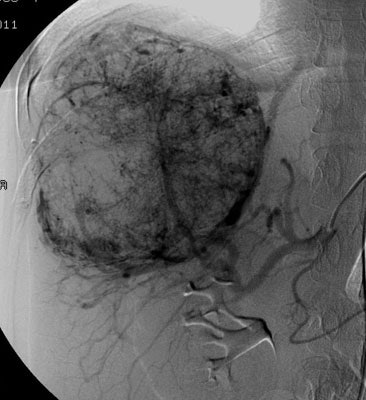

| Shunting to lung: The patient below was

referred for Y90-microshere therapy. A pre treatment TcMAA

hepatic arteriogram revealed a severe intrahepatic

arteriovenous shunt with a shunt fraction of 87%. Note the

intense lung activity. |